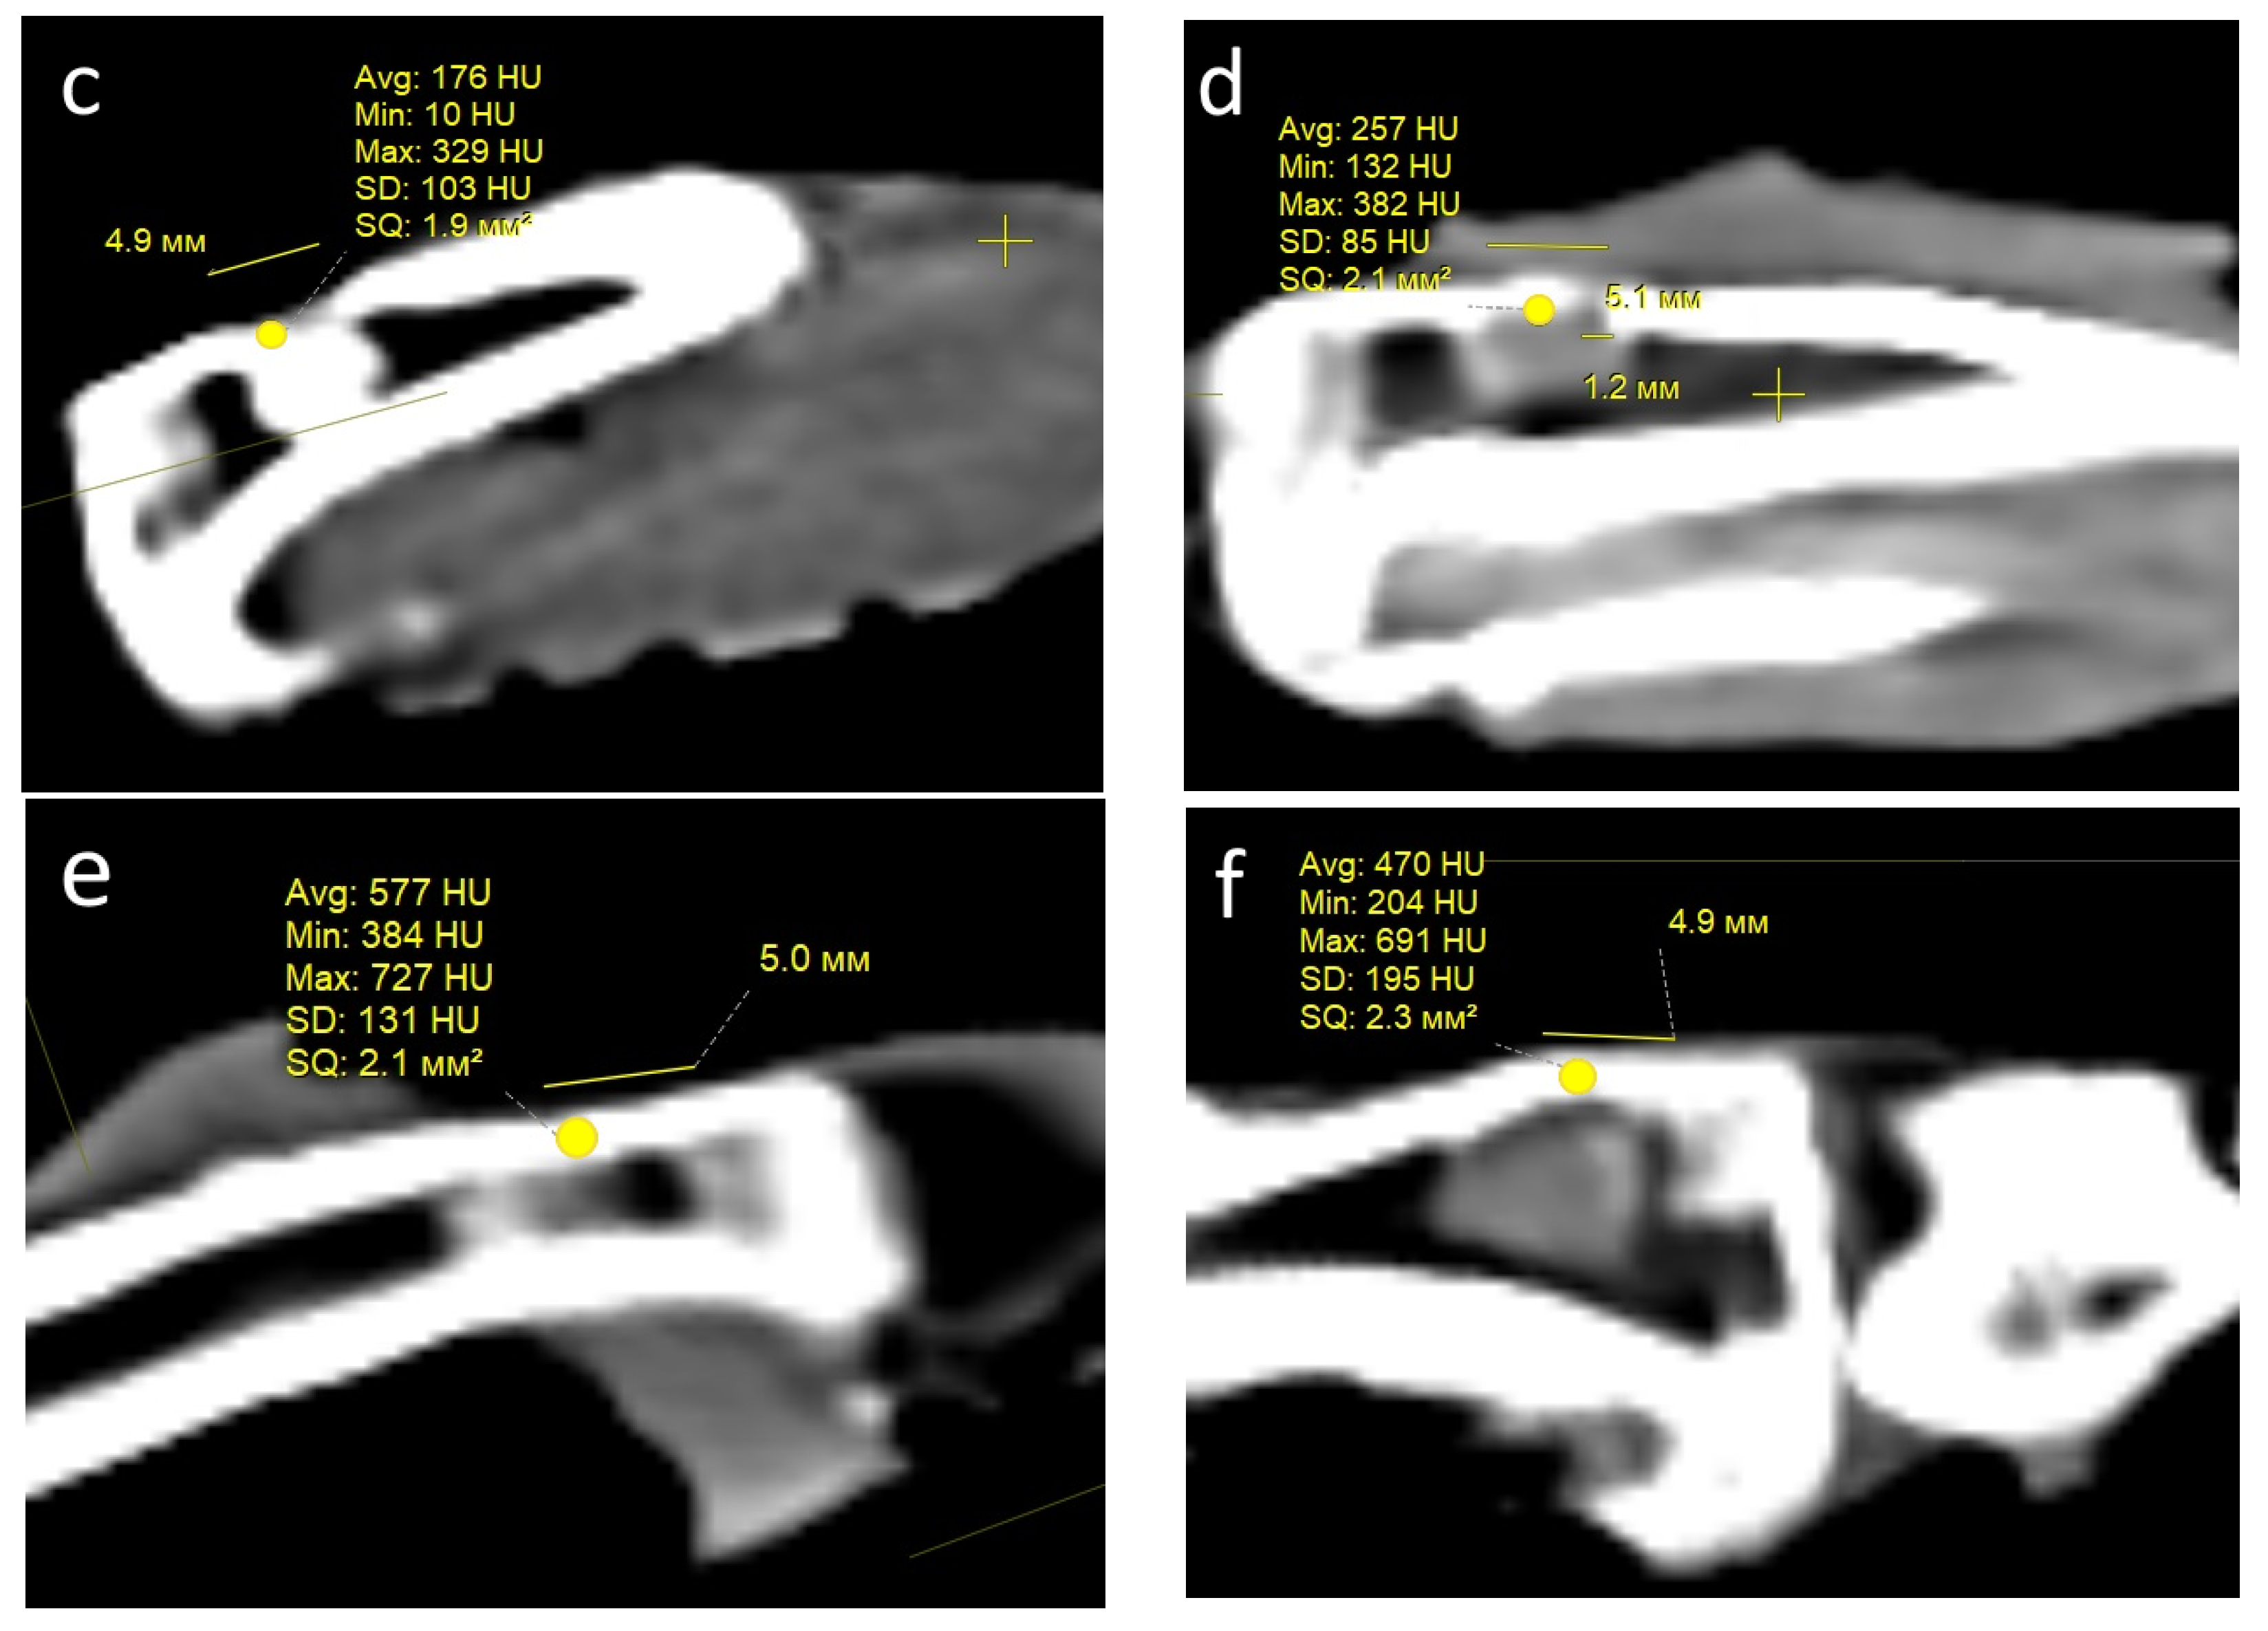

Condition of the defect area and computed tomography (CT) examination. One month after the operation, all rabbits in both groups showed signs of regeneration of the inflicted experimental bone defect in the form of a decrease in its size by 1–2 mm. The size of the defect, determined by CT measurements on the day of surgery, corresponded to the intraoperative measurements. At the CT densitometry assessment of the area after 1 month, the Hounsfield index among all rabbits in the control group (grafted osteoplastic matrix) was 69–271 HU. The average values of the X-ray density of the entire volume of the graft in the animals in this group were 142–229 HU, which indicated the heterogeneous nature of the cavity contents (Figure 8a). The values of this parameter in the experimental group (hybrid polymer) ranged from 15–89 HU. The average values of the X-ray density of the entire volume of the graft in the animals in this group were 31–67 HU (Figure 8b). This very insignificant scattering of values indicated the homogeneity of the graft. In the cortical bone structures adjacent to the defect, the Hounsfield index value was 680–720 HU.

Figure 8.

CT scan—section through the center of the implant in the sagittal direction, observed: at 1 month: (a) control, (b) experiment; at 2 months: (c) control, (d) experiment; at 6 months: (e) control; (f) experiment.

In the animals removed after 2 months, a further decrease in the size of the defect was seen, decreasing to an insignificant size of 1–2 mm. All animals in the control group (grafted osteoplastic matrix) had absolute values of the Hounsfield index from 10–457 HU. The average values of the X-ray density of the entire volume of the graft in the animals in this group were 171–231 HU (Figure 8c). The minimum value in the experimental group (hybrid polymer) was 96 HU, the maximum was 643 H. The average values ranged from 195–453 HU (Figure 8d). The measurements did not reveal any pathological changes in the cortical bone structures adjacent to the defects.

After 6 months, complete recovery of the applied defect was demonstrated in all animals in both groups. However, the Hounsfield index in the control group (grafted osteoplastic matrix) ranged from −60 to 910 HU and continued to demonstrate the heterogeneity of the graft tissue, along with occasional increases above the usual values for shin bone. The average values ranged from 305–577 HU (Figure 8e). The values of the X-ray density of the central part of the graft in the experimental group (hybrid polymer) ranged from 204–814 HU. The average values ranged from 426–615 HU (Figure 8f).

Therefore, the CT data, which includes CT densitometry of the central area of the graft, indicate that the processes of reparative regeneration in the animals in the control and experimental groups differed to some extent. In the control group, at all assessment points, the density of the graft was convincingly heterogeneous, and included areas where minimal X-ray shadow intensity persisted for 6 months. The graft placed into the bone defect in the rabbits in the experimental group demonstrated a stable increase in X-ray density, together with a less significant scatter between the minimum and maximum values of the X-ray shadow intensity.

Consequently, based on the CT image analysis, the authors determined the development of a more uniform structure; therefore, it was concluded that there were more active regenerative processes in the bone defects of the rabbits in the experimental group.